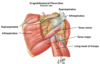

Deltoid

Origin : lateral third of the clavicle, the acromion, and the spine of scapula

Insertion : deltoid tuberosity of the humerus

Innervtion : axillary nerve

Because of its origin, the functions vary depending upon the part that is functioning. From a clinical viewpoint, its function as an abductor of the upper extremity is most significant.

Axillary nerve to deltoid enters posterior deep surface

The subacromial bursa (subdeltoid bursa) is located deep to the deltoid and acromion

Calcification of the supraspinatus tendon leads to inflammation of the bursa, causing pain on abduction of the upper extremity (painful arc syndrome).

Supraspinatus and Infraspinatus

Origin : respective fossae of the scapula

Insertion : greater tubercle of the humerus.

Innervation : suprascapular nerve

Blood supply : suprascapular artery, a branch of the thyrocervical trunk that originates from the subclavian artery

Teres minor

Origin : lateral border of the scapula

Insertion : greater tubercle of the humerus

Innervation : axillary nerve

Action : along with the infraspinatus, it laterally rotates the upper extremity

Teres major

Origin - inferior angle of the scapula

Insertion : medial lip of the intertubercular groove of the humerus

Innervation : lower subscapular nerve

The quadrilateral or quadrangular space.

Formed by three muscles and the medial border of the humerus.

The axillary nerve and the posterior circumflex vessels (artery and vein) forming the neurovascular bundle pass through this space to reach their destination.

The suprascapular nerve passes below the ligament, while the suprascapular artery and vein pass above.